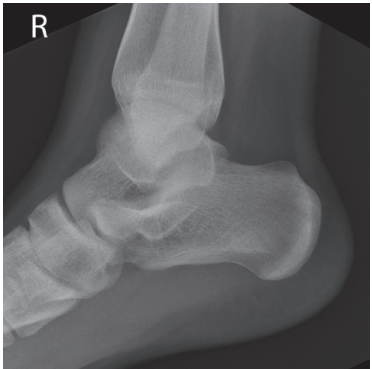

What are the issues with this ankle?

Foot is not dorsiflexed

the medial talar dome is demonstrated posterior to the lateral talar dome and the fibula will be demonstrated more anteriorly on the tibia

Internal rotation

the medial talar dome is demonstrated anterior to the lateral talar dome and the fibula is more posterior on the tibia

External rotation

The lateral talar dome is proximal to the medial dome, the height of the medial longitudinal arch appears less than it actually is, and the talocalcaneal joint is narrowed.

Proximal lower leg has been elevated